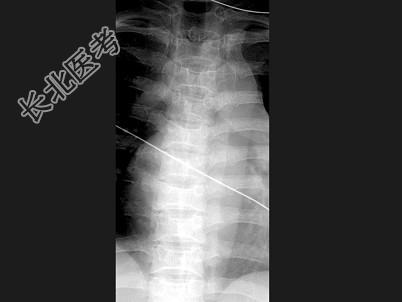

- 单项选择题女,24岁, 反复发作的骨骼肌肉痛,结合图像, 最可能的诊断是 ( )

A、镰状细胞贫血

B、地中海贫血

C、骨梅毒

D、白血病

E、椎间盘突出